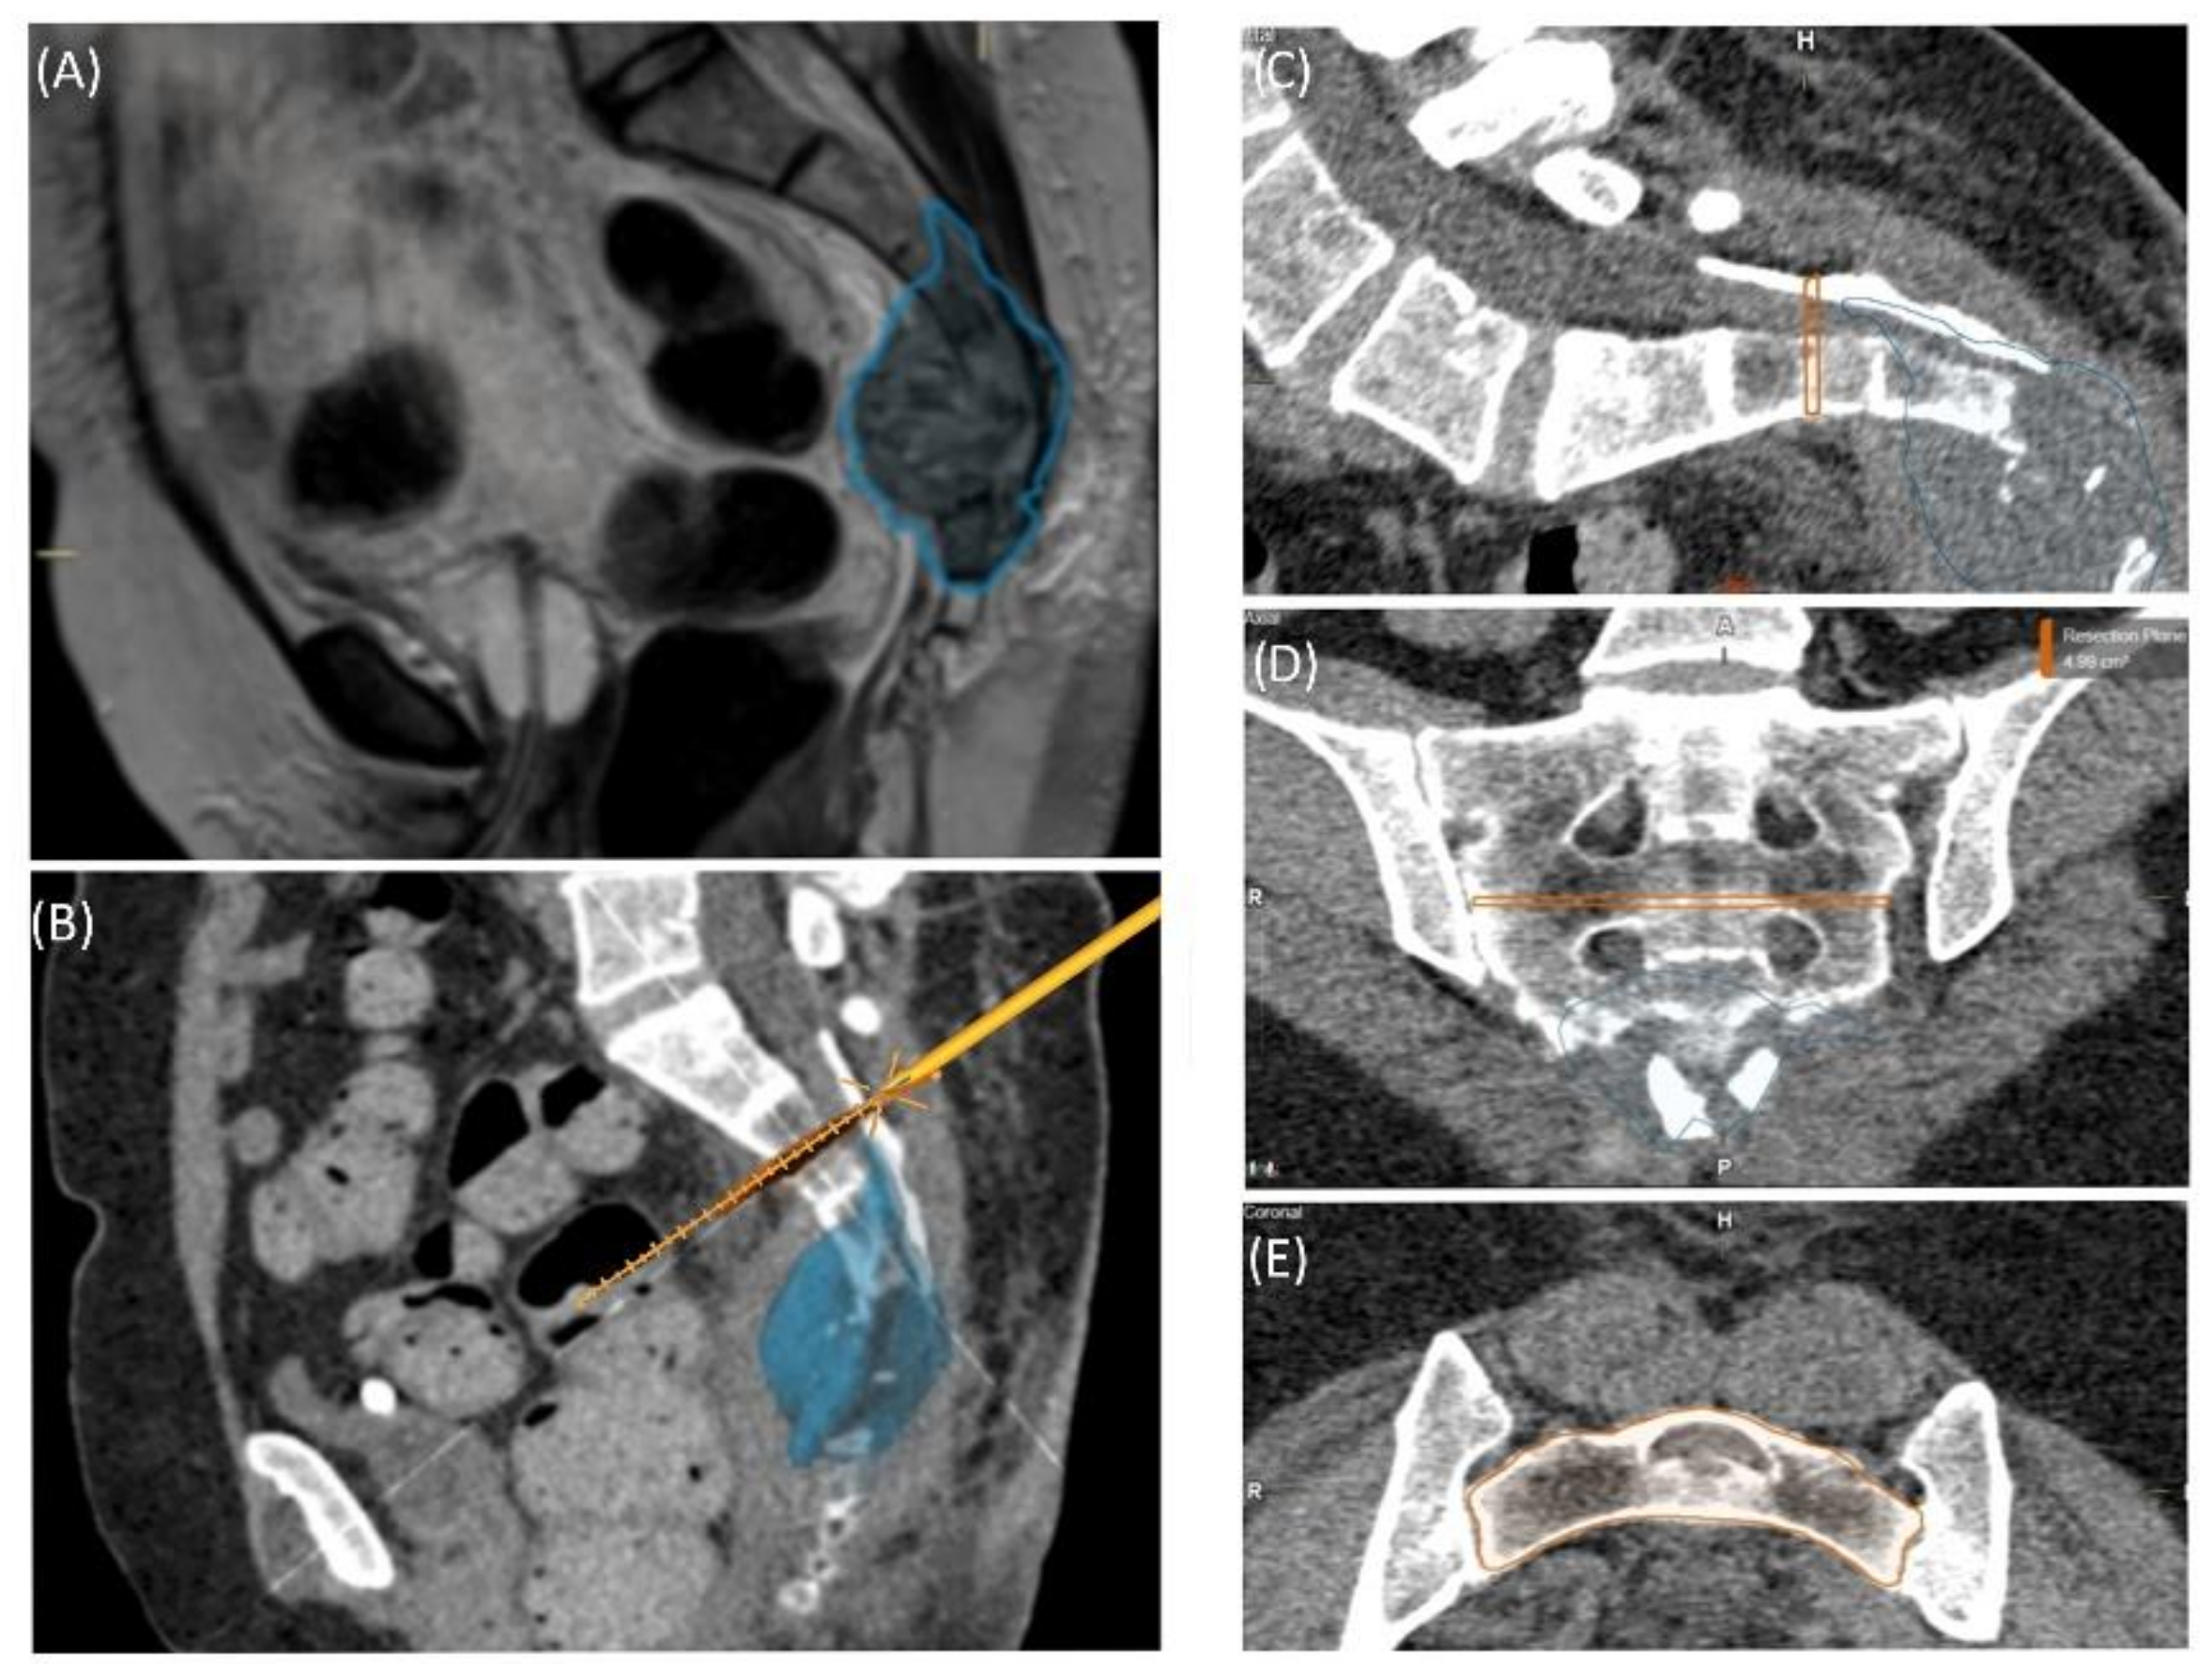

A 49-year-old female patient was diagnosed with an unclear sacral/coccygeal mass that was painful on palpation. The patient reported load-dependent coccydynia for 6–7 months with no typical radiculopathy, intact sensorimotor function, and regular fecal/urinary continence. After biopsy, high-grade osteoblastic osteosarcoma was diagnosed, and four cycles of neoadjuvant chemotherapy were administered according to the EUROBOSS protocol. Navigated resection of the sacral region S2/S3 to S5, including the coccyx (Figure 7), reconstruction of the defect of the rectal intestinal wall and reconstruction using a Vicryl mesh loaded with gentamycin chains, were conducted. Histopathologically, a R0 resection with a regression degree of 4 according to Salzer–Kuntschik was confirmed. Incontinence remained due to the resection of the sacral nerve roots. Because of reduced physical status, chemotherapy was not continued postoperatively.

Figure 7. Case 4: Segmentation and resection plane planning of a high-grade osteoblastic osteosarcoma of the sacrum; cross-sectional segmentation (AC) and 3D model with the resection plane as the volume (gray) (D,E).